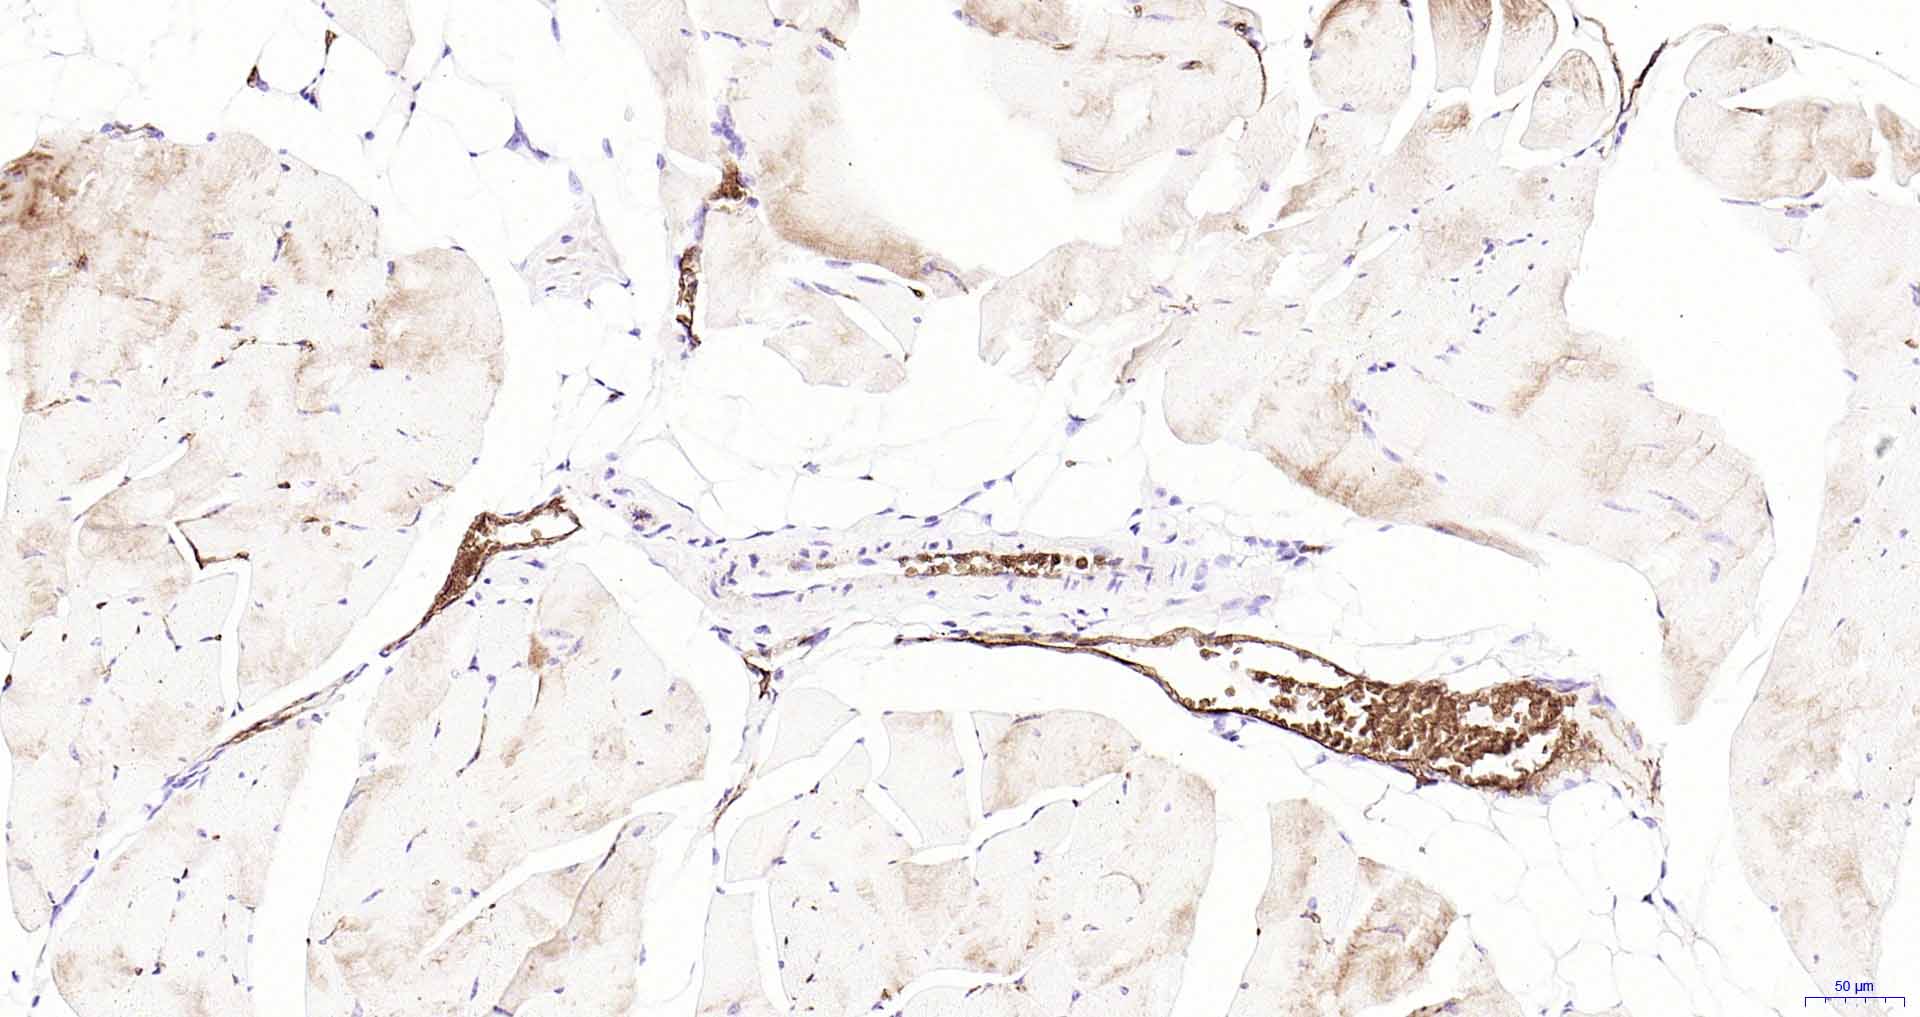

Paraformaldehyde-fixed, paraffin embedded Human Skeletal muscle; Antigen retrieval by boiling in sodium citrate buffer (pH6.0) for 15 min; Antibody incubation with AQP1 Monoclonal Antibody, Unconjugated(bsm-52909R) at 1:200 overnight at 4°C, followed by conjugation to the SP Kit(Rabbit, SP-0023) and DAB (C-0010) staining.

Paraformaldehyde-fixed, paraffin embedded Rat Skeletal muscle; Antigen retrieval by boiling in sodium citrate buffer (pH6.0) for 15 min; Antibody incubation with AQP1 Monoclonal Antibody, Unconjugated(bsm-52909R) at 1:200 overnight at 4°C, followed by conjugation to the SP Kit(Rabbit, SP-0023) and DAB (C-0010) staining.

Paraformaldehyde-fixed, paraffin embedded Mouse Skeletal muscle; Antigen retrieval by boiling in sodium citrate buffer (pH6.0) for 15 min; Antibody incubation with AQP1 Monoclonal Antibody, Unconjugated(bsm-52909R) at 1:200 overnight at 4°C, followed by conjugation to the SP Kit(Rabbit, SP-0023) and DAB (C-0010) staining.